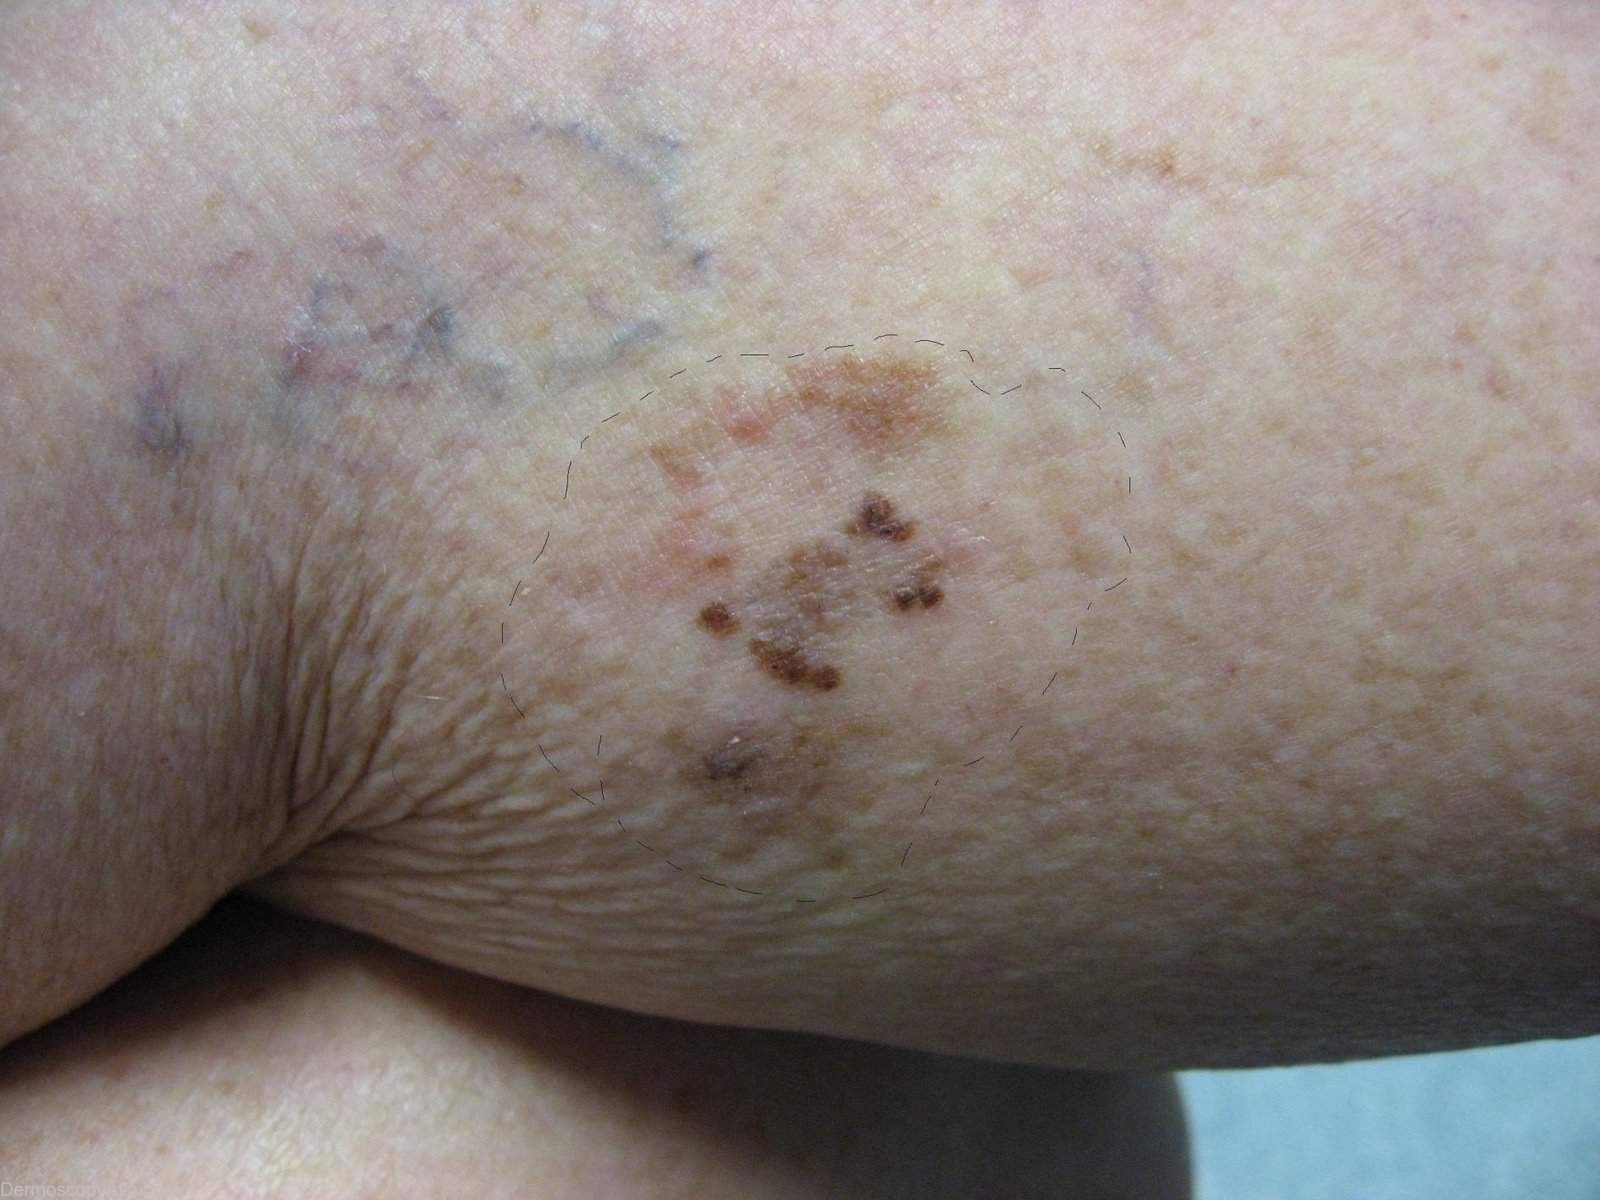

Site: Calf

Diagnosis: Melanoma regression

Description: Lesion on the calf. Clinically areas of regression are shown in both the pale and grey areas

Case courtesy of Dr Greg Canning This poorly demarcated lesion is approx 5 cm in diameter and has resided on the left proximal postero medial calf of it's 72 year old owner for as long as she can remember. On reflection however she thinks it may have enlarged somewhat over the years. She has been repeatedly reassured about it by the doctors who have treated her numerous non melanoma skincancers.